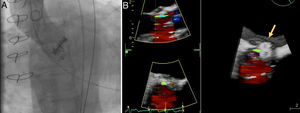

A 72-year old woman with a history of mechanical aortic prosthesis since 2010 and early infective prosthetic endocarditis (medical treatment) was hospitalized for acute heart failure in February 2015. Transesophageal echocardiography showed a severe paravalvular leak in the posterior portion of the aortic prosthesis (Figure 1A, arrow) and a pseudoaneurysm with fistulization to the left ventricle (LV) and aorta (Figure 1B, arrow), moderate mitral regurgitation and mild LV systolic dysfunction. Surgery was considered high risk and percutaneous closure of the paravalvular leak was attempted. The procedure was guided by fluoroscopy and transesophageal echocardiography. After confirming the stability of the device (Amplatzer® Vascular Plug II 12 mm/9 mm) and reduction of the paravalvular leak without functional compromise of the mechanical prosthesis (Figures 2A and 2B, arrow), the device was released. Minutes after deployment, the device migrated into the LV (Figure 3A, arrow and Supplementary data online, Movie S1). The device could not be retrieved (Figure 3B, arrow). Echocardiography images showed the device lodged beneath the posterior mitral leaflet, entrapped in the subvalvular mitral apparatus, with no significant compromise of mitral valve function (Figures 4A, arrow and 4B, arrow and Supplementary data online, Movie S2). Follow-up echocardiographies showed the device still in the same position. The patient died of sepsis due to a Clostridium difficile infection 58 days after admission (one month after the procedure). This case illustrates a rare and dramatic complication of percutaneous leak closure, but without significant hemodynamic impact on mitral valve and LV function.